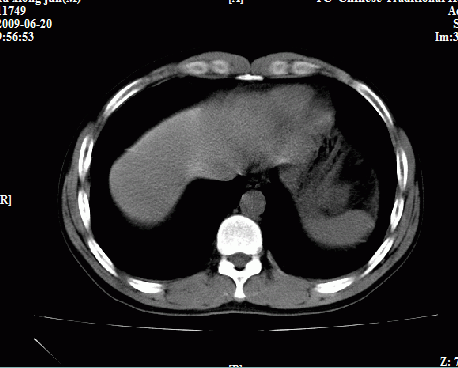

以下是引用随光逐影在2009-6-23 11:37:00的发言:[br]1)考虑胃癌;建议行胃镜检查进一步明确诊断。2)肝右叶肝内胆管结石(或钙化)。

以下是引用zxl51642在2009-6-23 11:31:00的发言:[br]胃大弯侧壁明显增厚呈软组织肿块,考虑胃癌可能性大,建议胃镜活检。